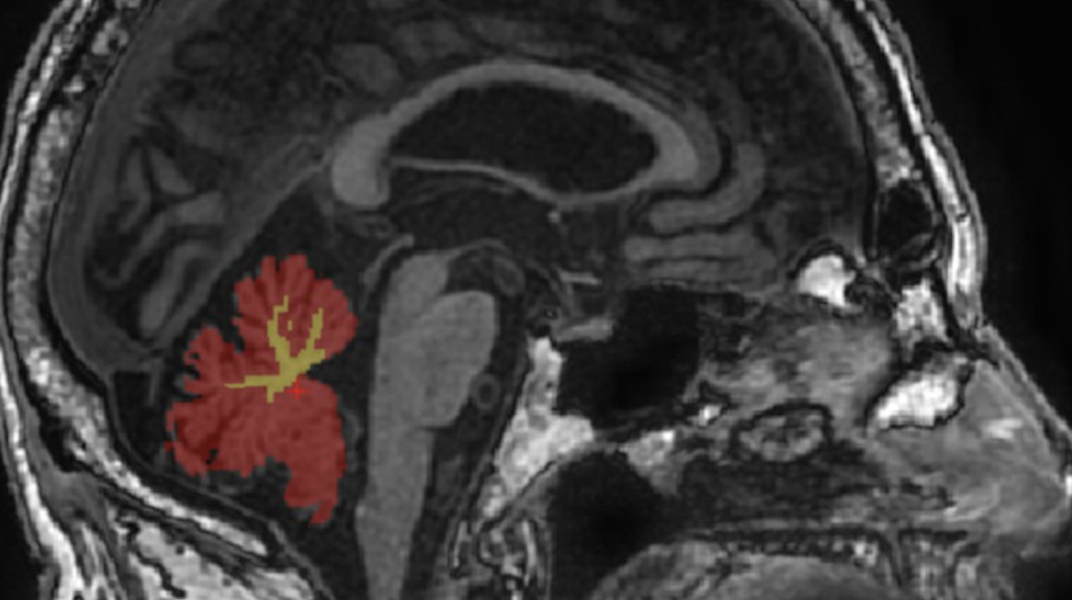

Magnetic resonance imaging (MRI) is a non-invasive technology for imaging human body. It is used daily in hospitals for aiding medical diagnosis; it is also widely used for studying human brain structure and function. Our lab develops methods to improve existing MRI techniques or create new forms of MRI. We are broadly interested in all things related to MRI: physics, hardware, image acquisition and clinical applications.